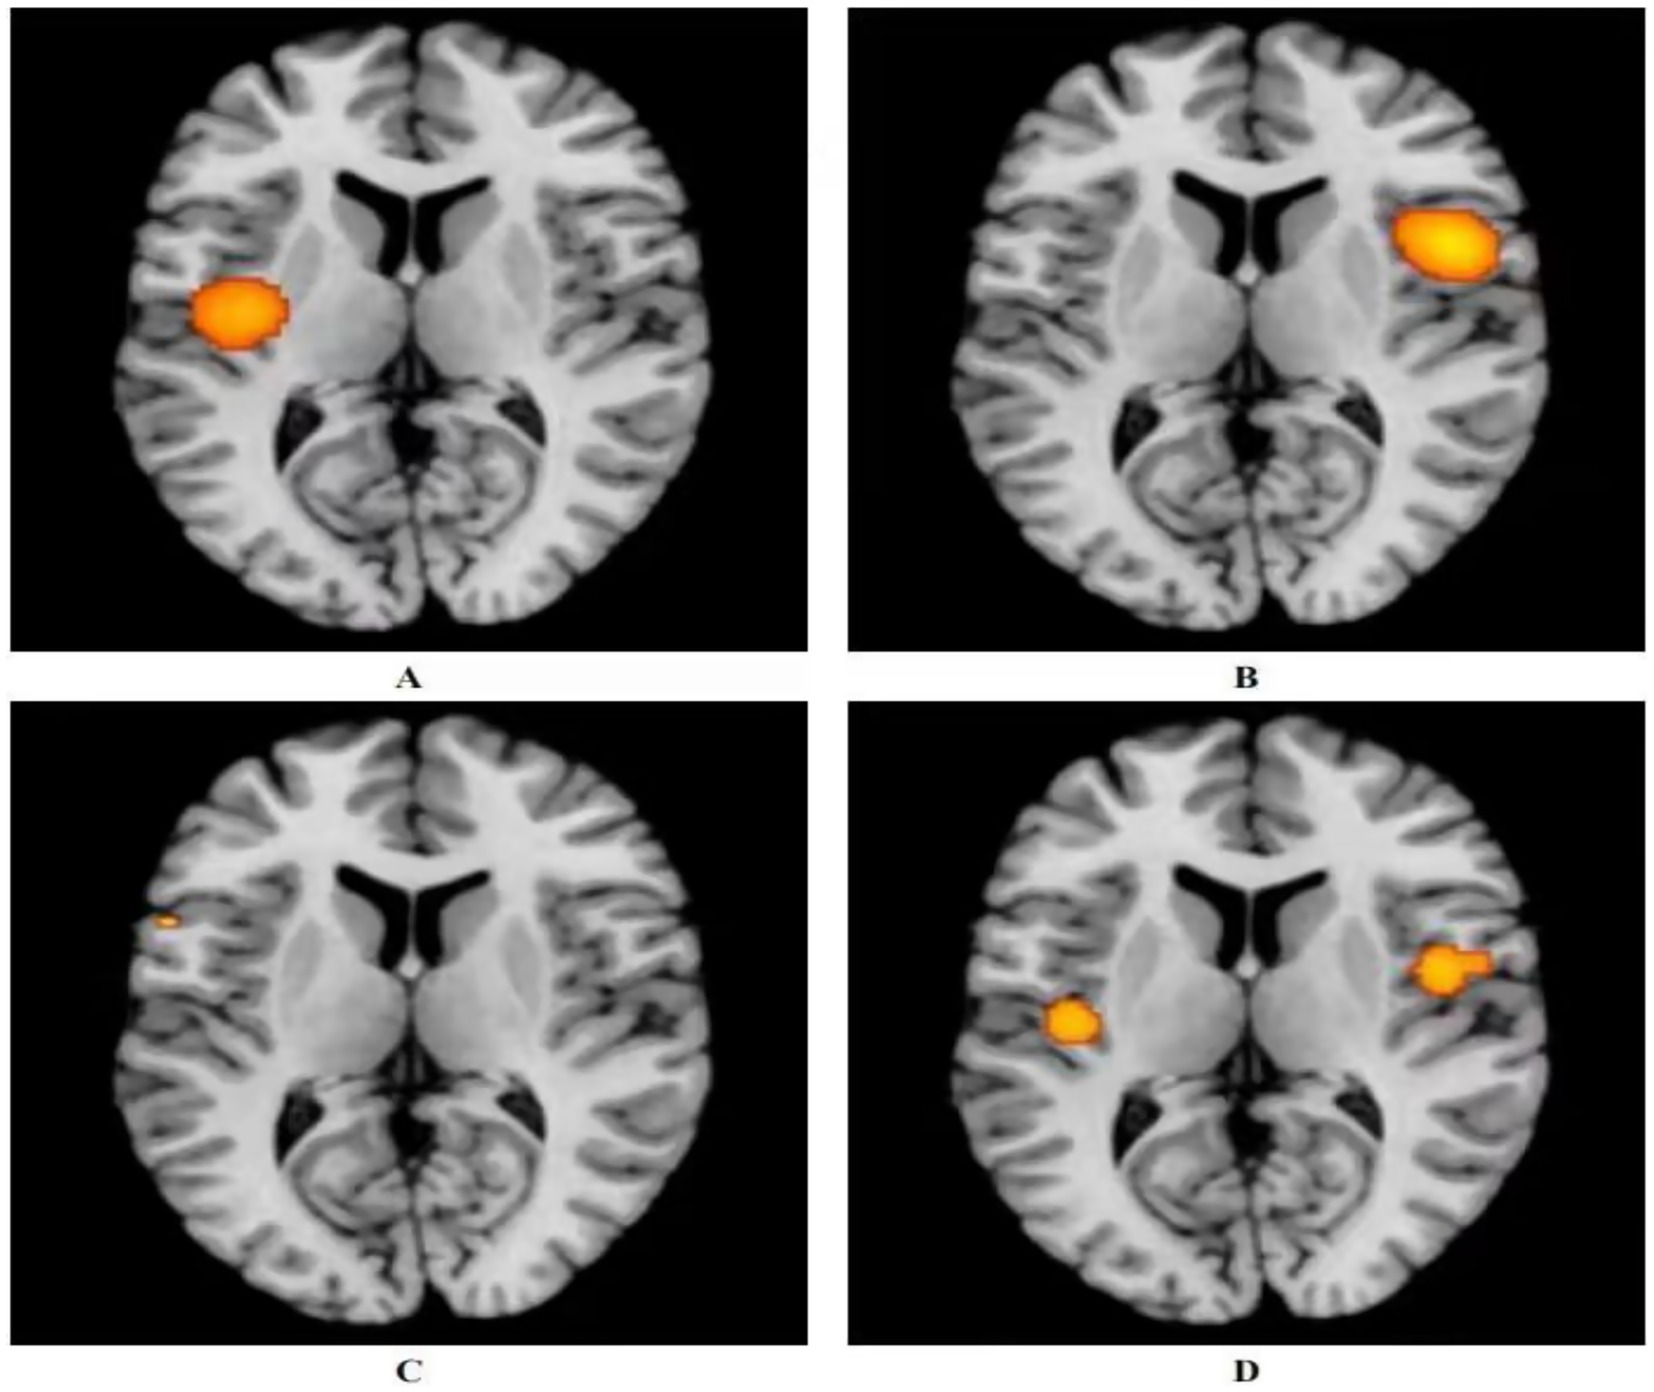

Three studies utilized acupuncture for the treatment of ANSLBP (39, 40, 42). Following the ALE meta-analysis of these articles, the results identified four clusters of positive activation and seven clusters of negative activation (Figure 3).

Figure 3. Activation of fMRI signals in cortical and subcortical structures in the acupuncture group. (A) Positive activation of brain regions after acupuncture with ANSLBP; (B) Negative activation of brain regions after acupuncture with ANSLBP; (C) Positive activation of brain regions after acupuncture with CNSLBP; (D) Negative activation of brain regions after acupuncture with CNSLBP.

Four clusters of positive activation were identified. The first cluster was located in the right cerebrum, specifically in the sub-lobar insula (Brodmann area 13), centered at coordinates x = 50, y = 6, z = 12 (ALE = 0.0022; p < 0.001; Z = 5.20). The second cluster was found in the right cerebrum, in the inferior parietal lobule (Brodmann area 40), centered at x = 62, y = −26, z = 34 (ALE = 0.0023; p < 0.001; Z = 5.39). The third cluster was situated in the right cerebrum, in the medial frontal gyrus (MFG) (Brodmann area 6), centered at x = 12, y = 0, z = 60 (ALE = 0.0019; p < 0.001; Z = 4.85). The final cluster was located in the right cerebrum, in the cingulate gyrus (Brodmann area 31), centered at x = 18, y = −24, z = 39 (ALE = 0.0019; p < 0.001; Z = 4.84) (Figure 3A; Supplementary Table 4).

Seven clusters of negative activation were identified. The first cluster was located in the left cerebrum, specifically in the sub-lobar insula (Brodmann area 13), centered at coordinates x = −41, y = −13, z = 15 (ALE = 0.0027; p < 0.001; Z = 6.36). The second cluster was found in the left cerebrum, in the cingulate gyrus (Brodmann area 32), centered at x = 0, y = 33, z = 21 (ALE = 0.0028; p < 0.001; Z = 7.03). The third cluster was situated in the left cerebrum, in the pulvinar of the thalamus, centered at x = −4, y = −30, z = −2 (ALE = 0.0019; p < 0.001; Z = 4.58). The fourth cluster was located in the right cerebrum, in the parahippocampal gyrus (Brodmann area 35), centered at x = 24, y = −27, z = −18 (ALE = 0.0019; p < 0.001; Z = 4.61). The fifth cluster was found in the right cerebrum, in the MFG (Brodmann area 8), centered at x = 14, y = 33, z = 44 (ALE = 0.0019; p < 0.001; Z = 4.57). The sixth cluster was located in the right cerebrum, in the angular gyrus (Brodmann area 39), centered at x = 54, y = −60, z = 39 (ALE = 0.0019; p < 0.001; Z = 4.61). The final cluster was situated in the left cerebrum, in the superior frontal gyrus (Brodmann area 6), centered at x = −14, y = 34, z = 52 (ALE = 0.0019; p < 0.001; Z = 4.57) (Figure 3B; Supplementary Table 5).

Seven studies utilized acupuncture as a treatment for CNSLBP (8, 41, 43–47). Analyzing the related articles revealed two clusters of positive activation and two clusters of negative activation (Figure 3).

The two positive activation clusters identified were as follows: one was located in the right cerebrum, specifically in the sub-lobar insula (Brodmann area 13), centered at coordinates x = 46, y = −2, z = 2 (ALE = 0.0019; p < 0.001; Z = 4.65). The other was found in the left cerebrum, also in the sub-lobar insula (Brodmann area 13), centered at x = −42, y = −16, z = 2 (ALE = 0.0015; p < 0.001; Z = 3.93) (Figure 3C; Supplementary Table 6).

The two negative activation clusters were located as follows: one was situated in the left cerebrum, in the precentral gyrus (Brodmann area 44), centered at x = −56, y = 12, z = 6 (ALE = 0.00095; p < 0.001; Z = 3.41). The other was located in the right cerebrum, in the middle frontal gyrus (Brodmann area 8), centered at x = 33, y = 40, z = 42 (ALE = 0.00095; p < 0.001; Z = 3.41) (Figure 3D; Supplementary Table 7).